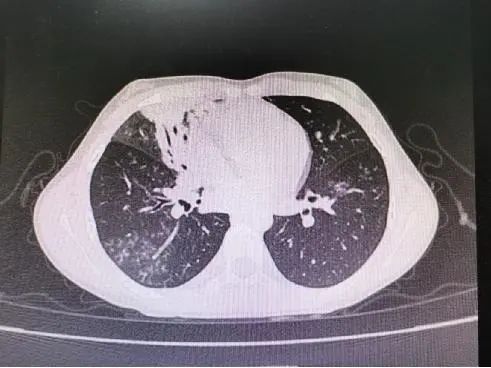

肺炎支原体肺炎的肺部体征及肺部影像学特点呈多样性改变,婴儿期可有湿性啰音,有时可呈梗阻性肺气肿体征。年长儿往往缺乏显著的胸部体征。肺炎支原体肺炎X线表现多样,有时仅为肺门阴影增重,多数呈不整齐云雾状肺浸润影,少数为大叶性实变影,可见肺不张,肺部阴影可呈游走性。CT大多数表现为磨玻璃样改变及肺间质性改变,体征轻微而胸片阴影显著,是本病特征之一。重症支原体肺炎时,可出现大叶性实变、坏死性肺炎、胸腔积液等。从目前住院患儿看,今年肺炎支原体感染所导致的大叶性肺炎明显高于往年。